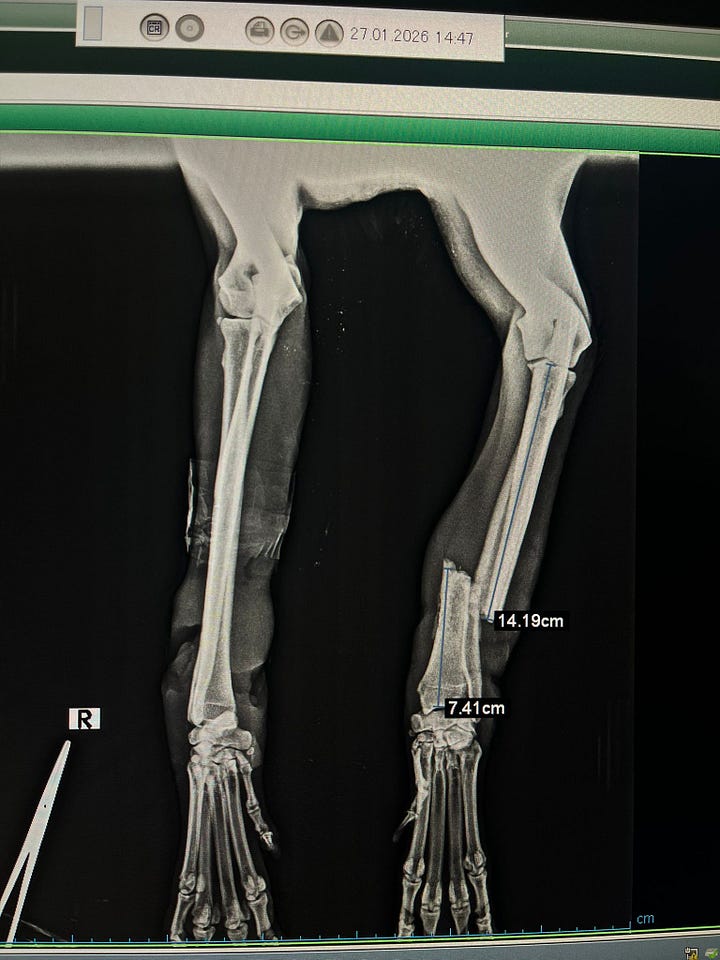

For Atış, our vets chose to use a plate alongside an external fixator to hold everything steady while the bone heals.

If you’ve seen the video, you’ll know it looks a bit frightening at first glance. Metal bars and pins never look gentle. But it’s actually one of the best tools veterinary surgeons have. It stabilises the bone from the outside without putting extra stress on damaged tissue.

There’s also something we always try to be open about with complex fractures like this: there are no guarantees. Even with a plate and an external fixator perfectly placed, healing isn’t something we can force it still depends on Atış’s body doing the work.

Bone needs strong blood supply, healthy surrounding tissue, and time. Because the injury is already two weeks old, circulation has been compromised, inflammation is higher, and the early healing that started in the wrong position can slow or disrupt proper repair.

Infection, implant failure, or the bone simply refusing to knit, what vets call a non-union are all risks we have to watch for. The fixator gives him the best possible chance, but it isn’t magic. It’s support, not certainty.